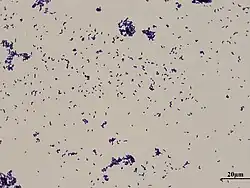

Corynebacterium xerosis

Genus: Corynebacterium

Species: Corynebacterium xerosis